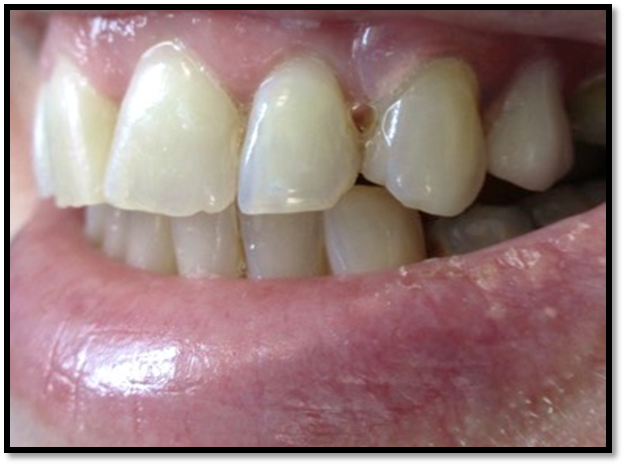

Resident Case Photos

The following are before and after photos of dental patients who have been treated by the residents at NYC Health + Hospitals/South Brooklyn Health. To apply to the program visit the Dental GPR Page and click on Application Information.

Crowns